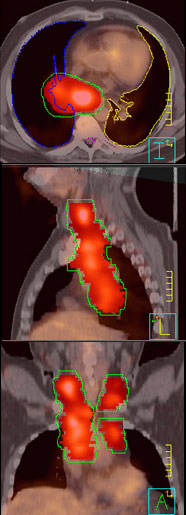

The combination of CT and PET imaging has significantly improved the ability to accurately map the distribution of cancer within the chest, and the newest generation of radiation therapy planning computers has the ability to take full advantage of both study types in the treatment planning process. This is done by co-registering or fusing the images from different planning studies in three dimensions on the same display. In this way the anatomic information provided by the CT and the cancer biological information provided by the PET study are combined in the computer. This in turn allows us to design the most accurate possible radiation treatment volume, which means a higher dose of radiation to the target volume, more accurately directed, with better sparing of surrounding tissues. This improves that chance of destroying the tumor without creating too much collateral injury to surrounding tissues.

Images on the right show how the radiation dose conforms to the tumor which appears as a white shadow, which is the PET scan image overlayed on the CT scan image. The area within the green envelope of radiation receives the highest dose.